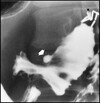

What pathology is shown here?

Tracheaoesophageal fistula

What are the white arrows pointing to?

The airway

What are the radiographic signs of a Tracheoesophageal Fistula?

-Connection of the fistula between airway and esophagus

-Large dilation of the esophagus